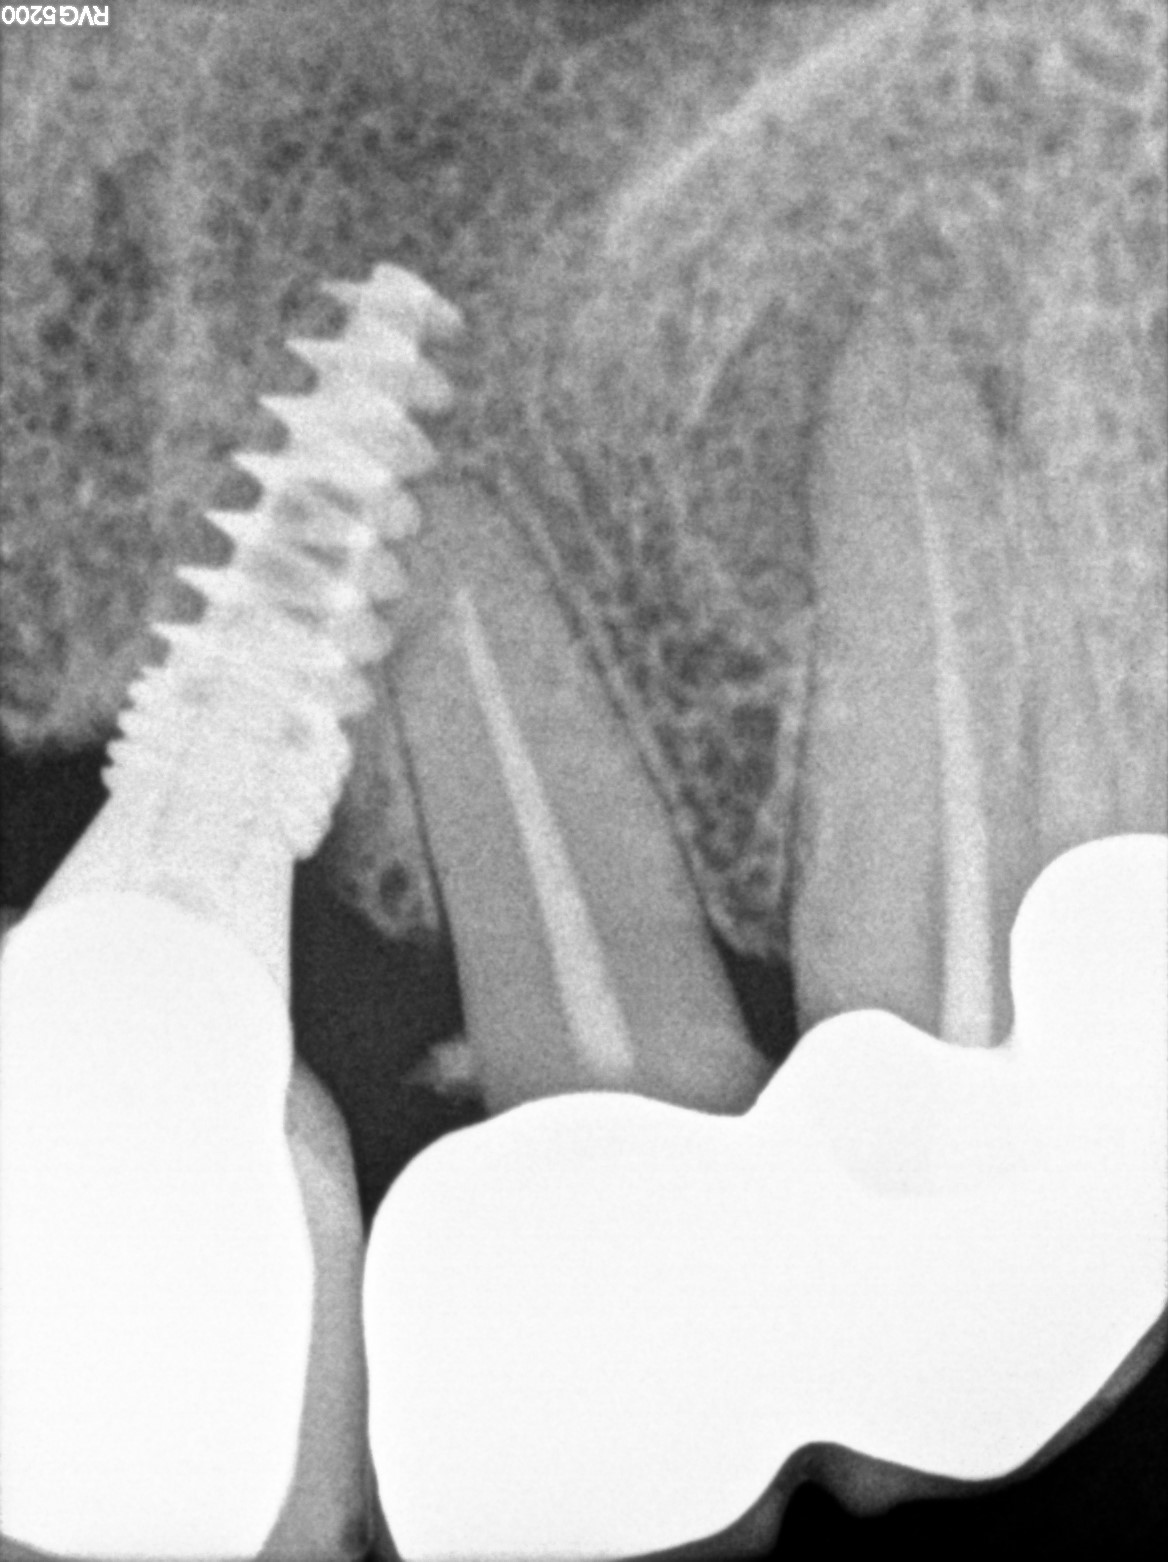

Dental Radiographs FHIR: DocumentReference · LOINC 24641-7

xray_1742374034.jpg

24641-7

| Dental implant placement | 234781005 | D6010 Surgical placement of implant body | — | 2025-03-19 | completed | full mouth implant done @ dr shoebs. came for checkup in 1st and 2nd quad. adv to return if any symptoms | |

| Dental implant placement | 234781005 | D6010 Surgical placement of implant body | — | 2025-03-19 | completed | implant hole filled |